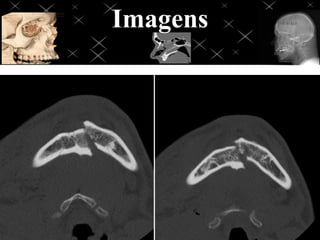

Face trauma

Aplicar os mesmos fatores técnicos e de posicionamento evidenciando a região a

ser estudada, ajustar o F.O.V de acordo com a região traumatizada, evitando

exposição desnecessária, se possível criar imagens tridimensionais para melhor

avaliação de fraturas.

OBS: para reconstruções 3D existem algoritmos

“certos” para que obtenha uma imagem 3D de

qualidade, nunca utilizar imagens com

algoritmos Bone, Lung e Edge para 3D de

visualização óssea.